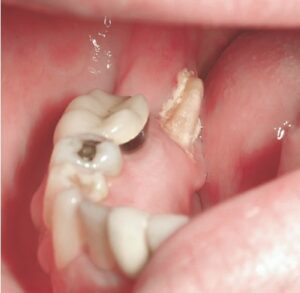

للأطفال والمراهقين، التوسيع السريع للفك العلوي (Rapid Maxillary Expansion ، RPE) طريقة مناسبة. في هذا الأسلوب، يوضع جهاز معدني على سقف الفم ويقوم بالتحريك اليومي لتوسيع الفك.

من مزايا هذه الطريقة: ألم قليل، تكلفة مناسبة، ونتائج سريعة خلال ۳ إلى ۶ أشهر. فتح الفك العلوي بدون جراحة بواسطة RPE مثالي بين ۷ و۱۲ عامًا. غالبًا ما يُدمج التقويم مع RPE لضيق الفك العلوي ويحتوي على تقويم تقليدي أو قوالب شفافة.